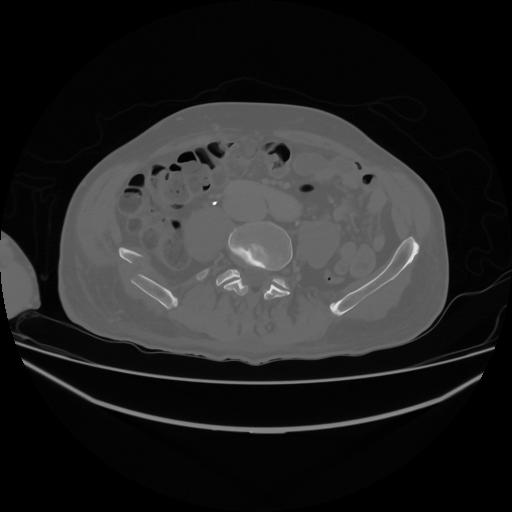

5 CUERPO,CE,Vol,1.0,CUERPO,,